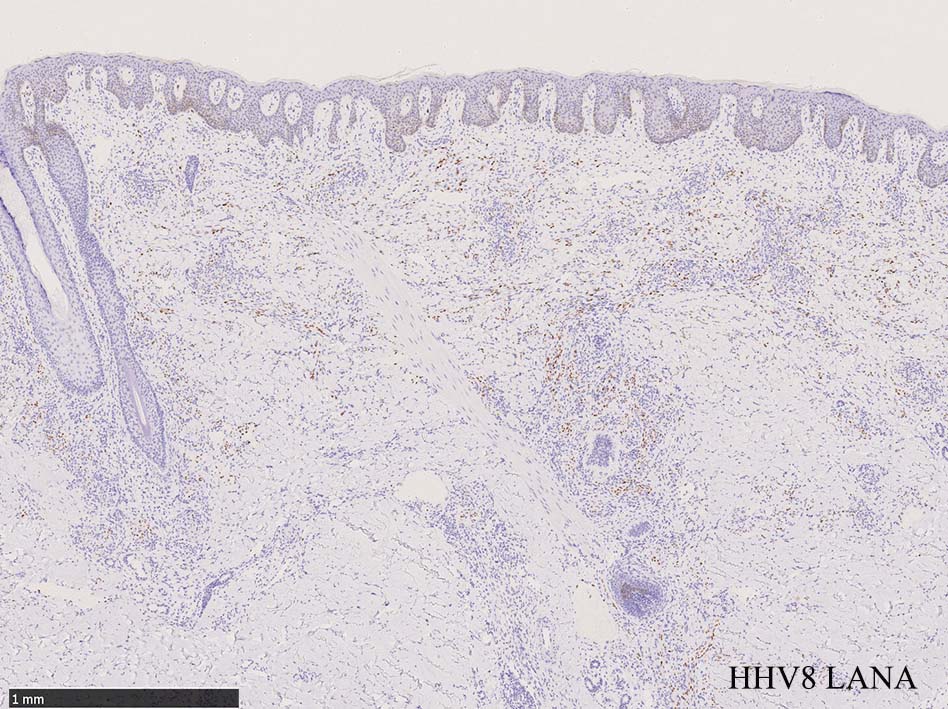

免疫染色, 分子病理学的検査

増生細胞はCD31, CD34, Factor Ⅷ, D2-40などが陽性を示す.

HHV-8の潜伏期関連抗原(HHV-8 Latency-associated nuclear antigen: HHV-8 LANA)が市販されており, 核が点状に染色される陽性所見がKaposi肉腫の確定診断に必須となっている.

組織からのPCRによるHHV-8の検出も診断に有用である.